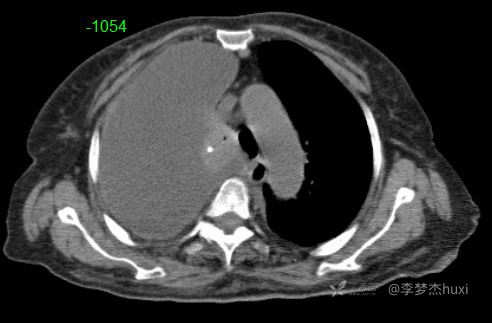

女性78岁,右侧满罐胸水,你绞尽脑汁也想不到的原因

体格检查:T:36.5℃;P:96次/分;R:20次/分;Bp:100/55mmHg,神清,呼吸平稳,浅表淋巴结不大,重度贫血貌,左肺叩清音,右肺叩浊音,右肺呼吸音消失,左肺呼吸音低,未闻及明显啰音,心率96次/分,律齐,无杂音。腹部平坦,软,全腹无压痛,无反跳痛及肌紧张,肝脾肋下未触及,双下肢水肿。

临床诊断:右侧胸腔积液